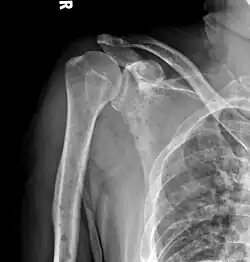

The diagnostic examination of a person with suspected multiple myeloma typically includes a skeletal survey. This is a series of X-rays of the skull, axial skeleton, and proximal long bones. Myeloma activity sometimes appears as "lytic lesions" (with local disappearance of normal bone due to resorption) or as "punched-out lesions" on the skull X-ray ("raindrop skull"). Lesions may also be sclerotic, which is seen as radiodense.[76] Overall, the radiodensity of myeloma is between −30 and 120 Hounsfield units (HU).[77] Magnetic resonance imaging is more sensitive than simple X-rays in the detection of lytic lesions. An MRI may supersede a skeletal survey, especially when vertebral disease is suspected. Occasionally, a CT scan is performed to measure the size of soft-tissue plasmacytomas. Nuclear Medicine Bone scans are typically not of any additional value in the workup of people with myeloma (no new bone formation; lytic lesions not well visualized on nuclear bone scan).

X-ray of the forearm, with lytic lesions -

Multiple myeloma in the upper arm -